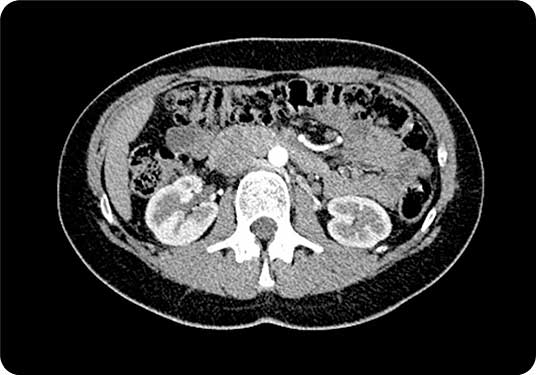

A CT scan (Computed Tomography) is a widely used diagnostic imaging procedure that combines advanced X-ray technology with sophisticated computer processing to generate detailed cross-sectional images of the body. These images provide precise visualization of organs, bones, blood vessels, and soft tissues, supporting accurate evaluation of injury, disease, and structural abnormalities.